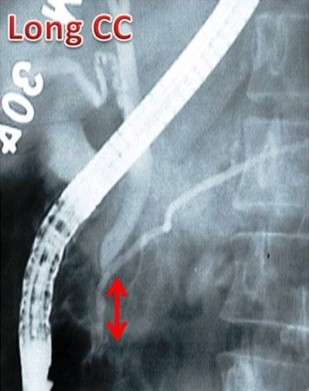

Figure 3. Three ERCP images showing the definition of a short common channel (short CC: channel length 3 mm), a long common channel (long CC: channel length 12 mm) and anomalous pancreaticobiliary ductal union (anomalous pancreaticobiliary ductal union: channel length 4 cm). CC: common channel; PBDU: pancreaticobiliary ductal union |

The reporting of the ERCPs was done in a stepwise fashion. The first step was to identify ERCPs in which both ducts were filled and pancreaticobiliary confluence was clearly identified in more than one image (inclusion criteria for study) (Figure 1). ERCPs in which only one duct (pancreatic or biliary) was filled or the confluence of the pancreatic and bile ducts was not clearly visualized were excluded from the study (Figure 1). Second, in those ERCPs included in the study, we then reported on whether the pancreatic and bile ducts opened into the duodenum separately or if the ducts were joined to each other and a common channel opened into the duodenum(Figure 2). Third, we measured the length of the common channel in the latter (Figure 3). To do so, we measured the actual length of the channel as it appeared on the images and corrected it with a magnification factor, as determined by the actual and imagined (as on images) width of the endoscope [15, 21]. If the corrected length of the united duct was less than 6 mm, it was reported as a short common channel. If the corrected length of the united duct was between 6 and 15 mm, it was reported as a long common channel. If the corrected length of the common channel was more than 15 mm, it was presumed that the ductal union had occurred outside the duodenal wall and such patients were reported as having anomalous pancreaticobiliary ductal union [20, 22]. For patients with anomalous pancreaticobiliary ductal union, we determined the pattern and angle of the ductal union. Anomalous pancreaticobiliary ductal union was reported as P-B type when the pancreatic duct appeared to join the bile duct and B-P type when the bile duct appeared to join the pancreatic duct. The angle of union was the actual angle at which the union occurred between two ducts [23].